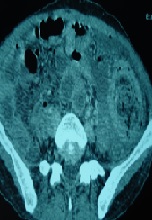

A Double Trichobezoar with a Gastric and Jejunal Locations: A Case Report

Fehmi Hamila, Fethi Derbel*, Jaballah Sakhri, Rached Letaief, Nefis